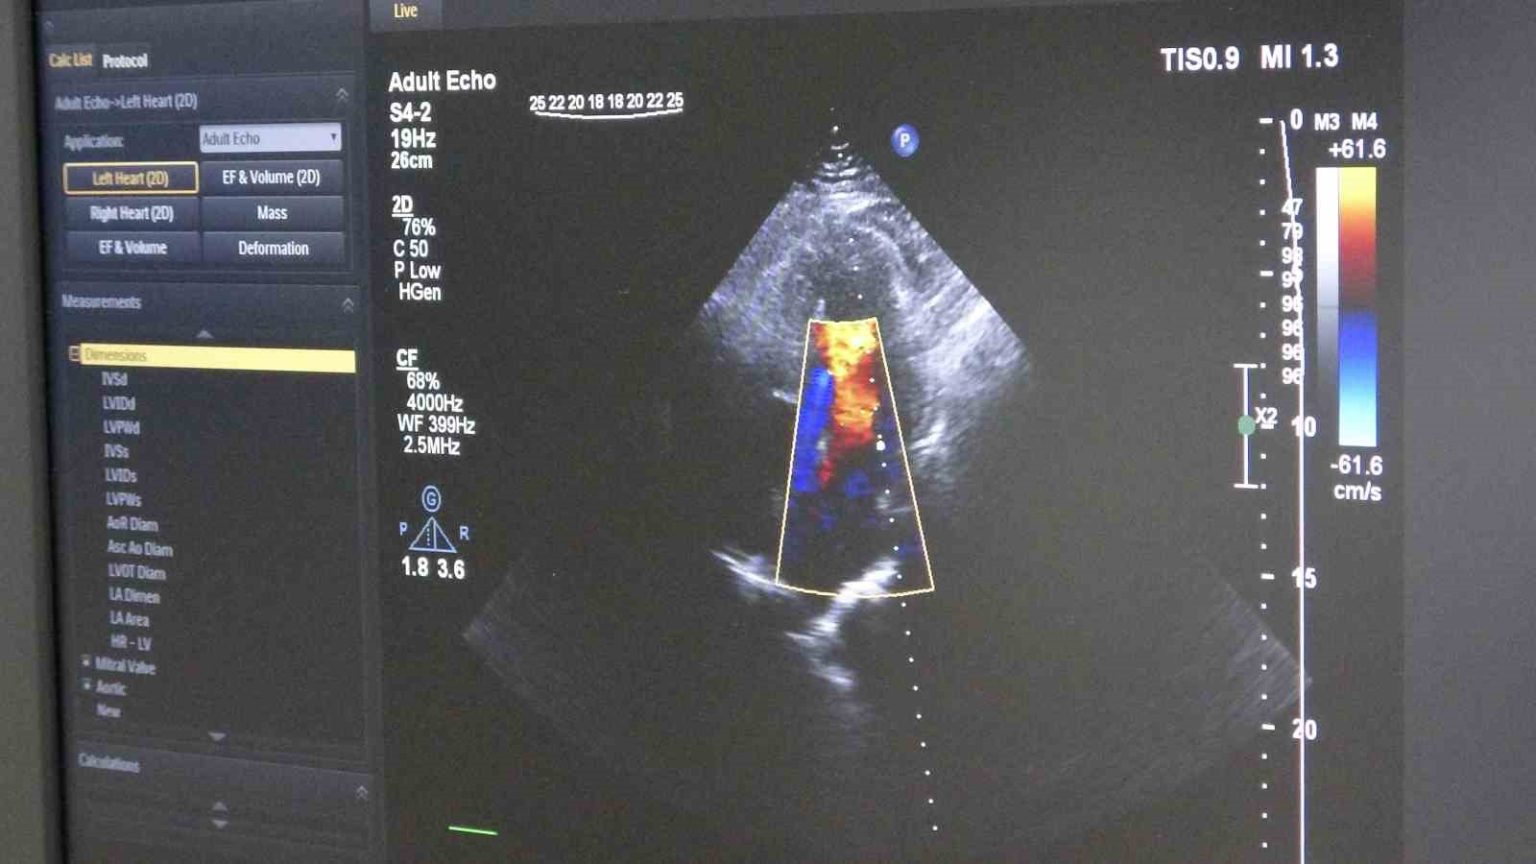

Gelişen teknolojiyle birlikte öne çıkan tedavi yöntemlerinden biri olan ilaç kaplı balon uygulaması, damara kalıcı metal yapı bırakmadan tedavi imkânı sunuyor. Bu yöntemde, özel ilaç kaplı balon damar içerisinde genişletilerek hem darlık gideriliyor hem de ilaç doğrudan damar duvarına etki ediyor.

Ordu Eğitim ve Araştırma Hastanesi Kardiyoloji Kliniği’ne göğüs ağrısı şikâyetiyle başvuran 55 yaşındaki erkek hastada yapılan anjiyografide, 3 damarda ileri derecede darlık tespit edildi. İlk değerlendirmede hastaya bypass ameliyatı önerildi. Ancak hastanın ameliyatı kabul etmemesi üzerine alternatif tedavi seçenekleri değerlendirildi. Yapılan detaylı incelemeler sonucunda hasta için ilaç kaplı balon yöntemiyle girişimsel tedavi planlandı. Uygulanan işlemle hastanın 3 damarındaki tıkanıklıklar stent kullanılmadan açılırken, hasta ise tedavinin 2’nci günü taburcu edildi.

Tedavi sürecinde damar yapısının ayrıntılı incelendiğini belirten Dereli, “İşlem öncesinde intravasküler ultrason (IVUS) ile damar duvarını değerlendiriyoruz. Ayrıca fraksiyonel akım rezervi (FFR) ile darlığın kan akımına etkisini ölçüyoruz. Bu yöntemler, doğru karar vermemizi ve başarılı sonuç elde etmemizi sağlıyor” diye konuştu.